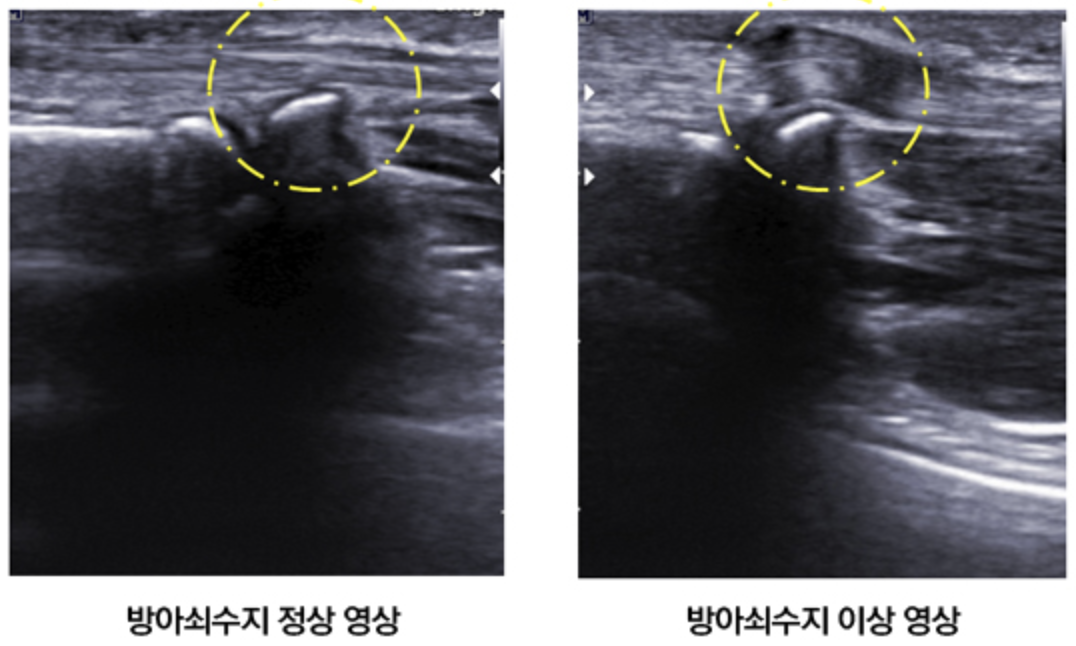

방아쇠수지의 진단은?

방아쇠 수지는 초음파 검사를 통하여 힘줄의 붓기, 염증을 확인할 수 있으며 구부렸다 펴는 동작을 통해 진단할 수 있습니다.